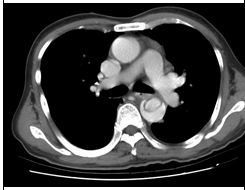

1. 病人62歲,男性,在6月8日清晨6時突然有嚴厲胸疼發生,以致醒來起床,隨即發生冒汗、噁 心、嘔吐及腹痛,乃急往醫院求治。病人有高血壓及貧血病史。理學檢查顯示急病面容,血壓250/100 mmHg,心跳67/min,心肺並無任何異常,但腹部腸蠕動聲減少,而且有腹肌難碰之狀,右腳踝dorsalis pedis脈動消失。胸部X光及心電圖如示。其他影像如圖 。血液檢查,AST 29 U/L;CK 102.0 U/L;CK-MB 22.4 U/L;Troponin I <0.04 μg/L;Amylase 80 U/L;Lipase 32 U/L;Na 3.3 mEq/L;K 3.3 mEq/L;D-dimer 12-24 μg/ml ;BUN 53.6 mg/dl;Creatinine 2.6mg/dl。病人服用Clondine (0.075 mg) 6#bid; Doxazosin (1 mg) 2#hs;Amlodipine (5 mg) 1#bid;Trichlorthiazide (2 mg) 1#qd;Minoxidil (10 mg)2#bid;Valsartan 1#qd; Metoprolol (100 mg) 1/2#qd。請問本病人最可能的診斷是: (A) 急性心肌梗塞 (B) 肺動脈栓塞合併肺動脈高血壓 (C) 急性心衰竭症 (D) 主動脈剝離 (E) 惡性高血壓